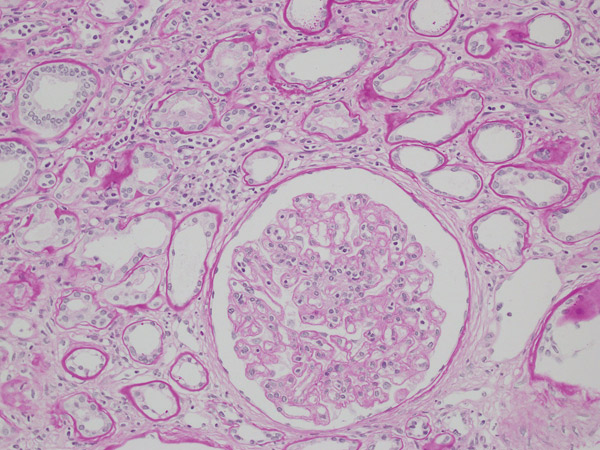

【目的】Caveolin-1(CAV-1)は慢性抗体関連型拒絶反応にて内皮細胞障害として発現する分子として報告されている。組織検体における発現の確認は凍結標本(IF)によるものが主体であったが、近年、CAV-1は中皮腫と肺腺癌を鑑別する抗体として、ホルマリン固定後検体に用いられるようになってきた。今回、ホルマリン固定後検体にて、慢性抗体型拒絶反応でのCAV-1の染色性について検討した。

【方法】ホルマリン固定後検体にて、酵素抗体法でCAV-1の染色を行った。評価は、傍尿細管毛細血管(PTC)、糸球体内毛細血管(GBM)での発現を3段階分類した。ptc、cg、ptcbm、C4dのBanffスコアと比較検討した。

【結果】レシピエントの移植時年齢の中央値は33歳(10-51)、生検時年齢の中央値は42歳(28-55)、男女比は7:4(男:女)、ドナー年齢は55歳(33-63)、男女比は7:4(男:女)であった。全例がABO適合腎移植で、biopsyprovenの急性抗体関連型拒絶反応の既往のある症例は8例であった。それぞれのPTC / cgスコアは3:3 / 4例、2:1 / 4例、1:7 / 3例、0:0 / 0例であり、ptcbmスコアは2:1例、1:10例、0:0例であった。またptcにおけるC4dとCAV-1の発現は、C4dスコア3:0例、2:2例、1:5例、0:4例、CAV-1スコア3:9例、2:2例、1:0例、0:0例であった。またGBMにおけるそれぞれの発現は、C4dスコア3:8例、2:2例、1:0例、0:1例、CAV-1スコア3:7例、2:4例、1:0例、0:0例であった。電顕が施行された6例中5例で内皮下の浮腫状変化を認めた。

【結論】CAV-1はC4dと比較し、GBMでの発現は同等であった。ptcでのC4dの発現は乏しかったが、CAV-1は全例でスコア2以上の発現を認めた。また、ptc、cgの変化の乏しい症例においてもCAV-1の発現を同定することができ、光顕で確認される組織変化が生じる以前のより早期からCAV-1の発現が同定される可能性が示唆された。以上より、CAV-1はホルマリン固定後検体でも良好な染色性をもっており、内皮障害の同定に有用である可能性が示唆された。 |